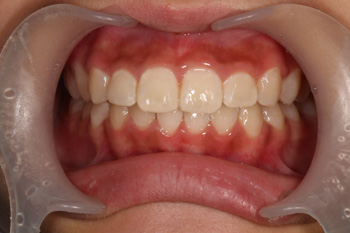

歯列育形成によるお子様の叢生の歯並び治療の症例

小さな頃から検診で通っていただいている患者様です。昔から歯の健康に気をつけておられましたが、歯並びについては悩んではおられるもののなかかな矯正には踏み出せずにおられました。 11歳になられてから、お母様から矯正についてのご相談があり、トリートメントコーディネーターからの説明を受けた後、矯正相談を希望されました。 11歳という年齢は、小児矯正(Ⅰ期矯正)を始めるには微妙な年齢ですが、矯正医の診断を受け、Ⅰ期矯正による咬合育形成という顎を拡げて歯を並べる矯正をスタートしました。

After

小児矯正と成人矯正の違いは、歯を並べるスペースを拡げて作るか抜いて作るかというところがあります(※成人後も抜歯無しで並べれる場合もあります)。大人になってからの矯正では外科手術以外顎の骨格を変えることはできませんのが、Ⅰ期矯正を行うことで歯を並べるスペースを確保し、抜歯せずに歯を並べることが可能となります。約2年で、歯を並べるスペースを確保し、きっちり歯も並びました。

治療の内容 歯列育形成によるお子様の叢生の歯並び治療。

期間・回数 2年・23回(カウンセリング・検査含む)

費用 自由診療:歯列育形成 総額 580,000円(調整料36回分含む)税込701,800円